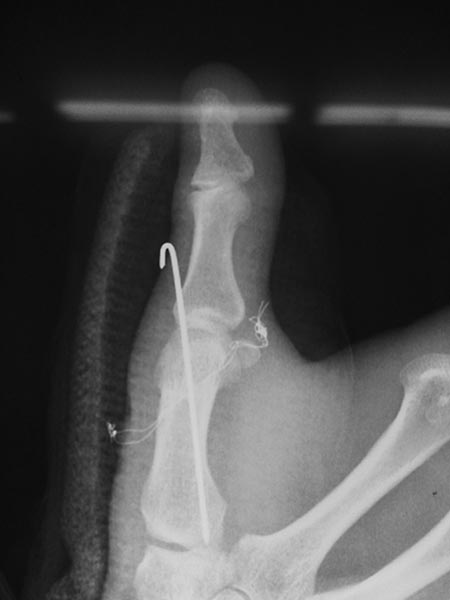

Уважаемые коллеги!!! Помогите разобраться!!! В отделение поступил

пациент, которого оперировали в Тайланде 11 ноября 2013г. Травма

получена в результате падения с опорой на кисть. Со слов пациента

оперирован по поводу вывиха в пястно-фалангового сустава, вывих

закрытый, без повреждения сухожилий (первичных снимков нет). Сделали вот

такой остеосинтез (см. фото). Не можем понять для чего проволока???

Пациенту рекомендовали тайландскиие врачи удалить проволоку через 2

месяца со дня операции, проволока выведена на кожу с 2-х сторон.